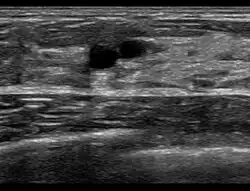

Fibrozystische Veränderungen entstehen im Drüsen- und Gangepithel aufgrund der wechselnden Hormoneinflüsse im weiblichen Zyklus. Zysten entstehen dabei aus erweiterten Milchgängen und Drüsenläppchen (Lobuli) und können wenige Millimeter bis mehrere Zentimeter groß werden. Die meisten tastbaren „Knoten“ in der Brust sind Zysten. Die Zystenwand besteht aus atrophiertem Drüsenepithel, das etwa ebenso selten entartet wie normales Drüsengewebe. Zysten sind also kein Risikofaktor für die Entstehung von Brustkrebs.